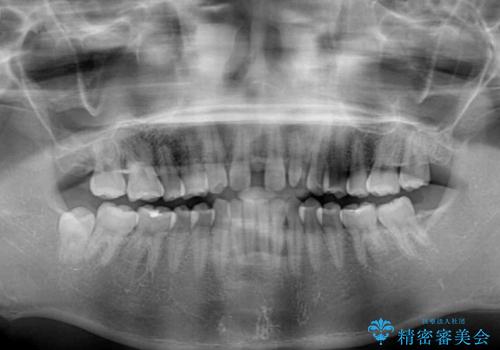

診察の結果、前歯が1本欠損しており、さらに矮小歯(通常よりも小さい歯)が1本存在していました。

欠損による前歯のスペースが大きかったため、事前にワイヤー矯正で前歯の位置を大きく動かし、その後は上下をインビザラインで整えることとしました。

矯正治療後には欠損部はオールセラミックブリッジに、矮小歯はオールセラミッククラウンにて補綴することとしました。

前歯のスペースは、堅い線維の通った歯肉があり、幅も大きかったことから、歯肉切除を行った上でワイヤー矯正により移動を行いました。また、上唇小帯も歯間部付近まで付着していたため、合わせて切除しました。